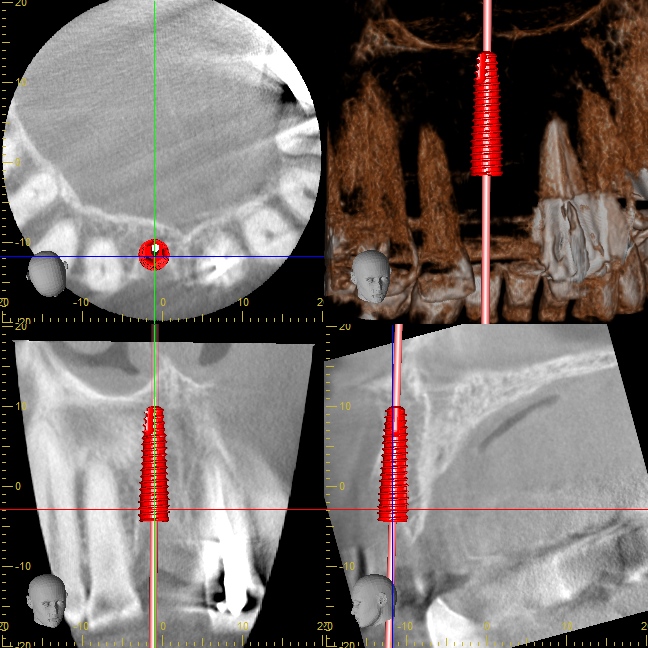

オペ前のシミュレーション

ほとんどの医院さんで

・前歯のインプラントが難しい

・骨が無いから、骨を造る処置が必要

・治療期間が1年くらい

と言われてしまう理由は、インプラントの外側(唇側)に骨が足りないことが多いからです。

今回の症例でも、右下のCT画像を見て頂くと分かるように、インプラントの外側(唇側)の骨がペラペラで薄いことが分かります。

骨が少なくても安全に骨を増やせます。

骨を増やす手法としては

・人工骨移植

・自家骨移植(ご自分の骨の移植)

のいずれかが一般的に行われています。

しかし、人工骨移植には感染リスクが伴います。

また、移植した人工骨が生着しない可能性もあります。

自家骨移植には、手術箇所が増えるデメリットがあります。

インプラントを埋め込む部位に加えて、口腔内のどこかから骨を採取するため、傷口が2箇所になり痛みが倍になってしまいます。

以上の理由により、私はできるだけ骨移植を行いません。

その代わりに行なっている手法が、Densah® Burの逆回転ドリリング。

骨を削るドリルを正回転で回すと、骨の削片が浮き上がってきます。

骨を削るドリルを逆回転で回すと、骨の削片が内部に押し込まれることで、むしろ骨が増えます。

骨を削るのではく、骨を圧縮し広げることで、前歯のインプラントオペがシンプルかつスムーズに終わります。